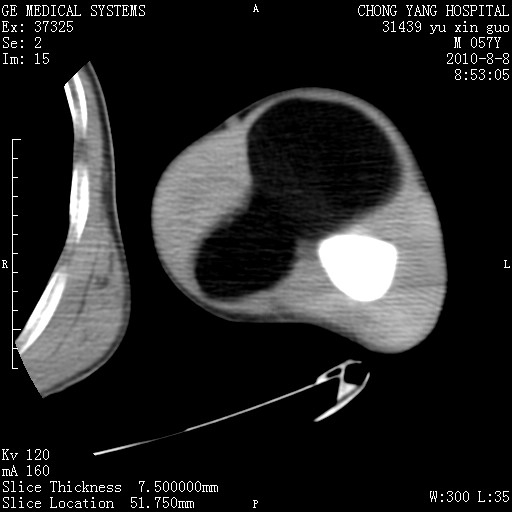

标题: CT28267:M57Y 上臂包块8年余。 [打印本页]

标题: CT28267:M57Y 上臂包块8年余。

上臂软组织内脂肪瘤。

包膜光滑、完整的脂肪密度肿块,支持脂肪瘤。